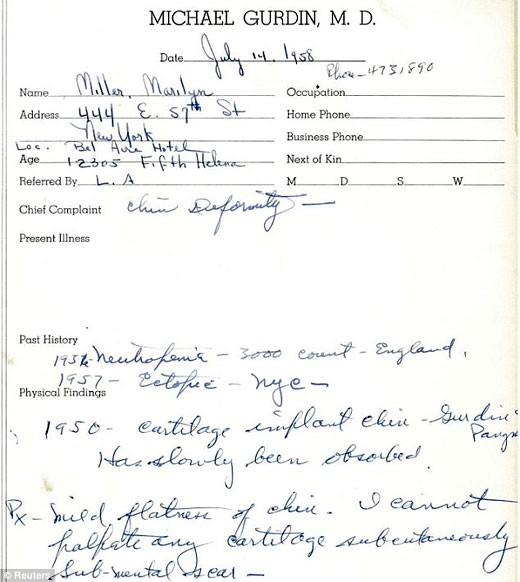

Marilyn Monroe: belleza... ¿natural?

El médico Michael Gurdin sacó a la luz pública reveladores informes médicos, que serán subastados en Beverly Hills, que demuestran que la actriz se sometió a un implante de cartílago en su barbilla en 1950 con el fin de potenciar su atractivo físico.

Las notas escritas por el Dr. Michael Gurdin comenzaron en 1958, cuando la actriz lo consultó por una "deformidad en el mentón". Aquí figura con su nombre de casada, Marilyn Miller, ya que había contraido matrimonio con el escritor Arthur Miller.

A las reveladoras notas escritas por el médico Michael Gurdin, supuestamente encargado de llevar a cabo la operación quirúrgica en 1950, se suman varias pruebas de rayos X realizadas el 7 de junio de 1962, dos meses antes del fallecimiento de la artista, en las que se pueden apreciar desde diferentes ángulos los huesos faciales de Marilyn, sus conductos nasales y su paladar.

"Nadie pensaba que Marilyn había acudido a un cirujano plástico. Hasta ahora eran meras especulaciones y siempre se había creído que poseía una belleza natural. Además, en esa época (años cincuenta) casi nadie se operaba, son técnicas que se consideran muy nuevas", comentó Martin Nolan, director de la casa de subastas Julien's Auctions, encargado de la venta de los citados informes médicos pertenecientes a la estrella del celuloide.

Radiografías de Marilyn Monroe, bajo el nombre de Marilyn DiMaggio, sacadas por un joven médico en 1954.

Se espera que estos reveladores documentos, entregados por el propio cirujano a un anónimo en forma de presente, lleguen a alcanzar entre los 15 y 30 mil dólares en la esperada subasta.